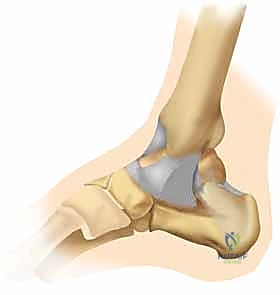

الأربطة والميكانيكا الحيوية

العظام وحدها لا تكفي للحفاظ على استقرار المفصل. هناك شبكة قوية من الأربطة (Ligaments) التي تربط هذه العظام ببعضها. عندما يحدث كسر ثنائي الكعب، فإن هذه الأربطة غالباً ما تتعرض للتمزق أو الشد العنيف، مما يؤدي إلى فقدان كامل لاستقرار المفصل (Ankle Instability).

عند كسر الكعبين (الداخلي والخارجي معاً)، يفقد الكاحل الحلقة التي تثبت عظمة الـ Talus في مكانها. هذا الانزياح، ولو كان بملليمترات قليلة، يؤدي إلى تغيير جذري في توزيع الضغط على غضروف الكاحل، مما قد يؤدي إلى خشونة مبكرة وتآكل في المفصل إذا لم يتم رده وتثبيته بدقة متناهية.